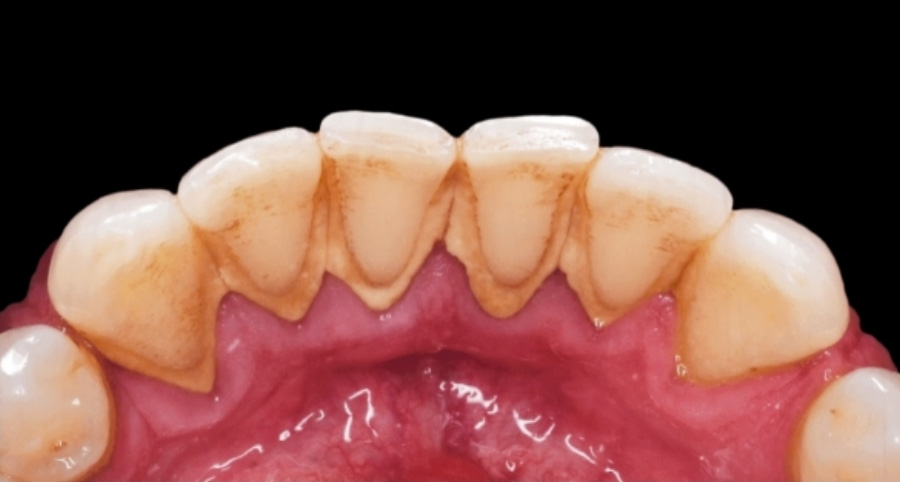

치석(齒石)이란 치경부(齒頸部)에 침에서 분비된 석회분(石灰分)이 부착해서 굳어져 생긴 물질인데 때때로 제거해 주어야 한다.

‘附齒有黃黑色物 似爛骨之狀者名爲齒牀 治齒者 先看有此物卽用疳刀掠去之 否則齒不着齦也’

치아(齒牙)에 황흑색(黃黑色)인 물렁뼈 비슷한 것이 부착된 것을 치상(齒牀)이라고 하는데 이를 고치는 사람은 무엇보다도 먼저 이것이 있는가를 살펴서 수술용 메스로 긁어내도록 해야지 그렇지 않으면 이가 들떠서 잇몸에서 떨어지게 된다.